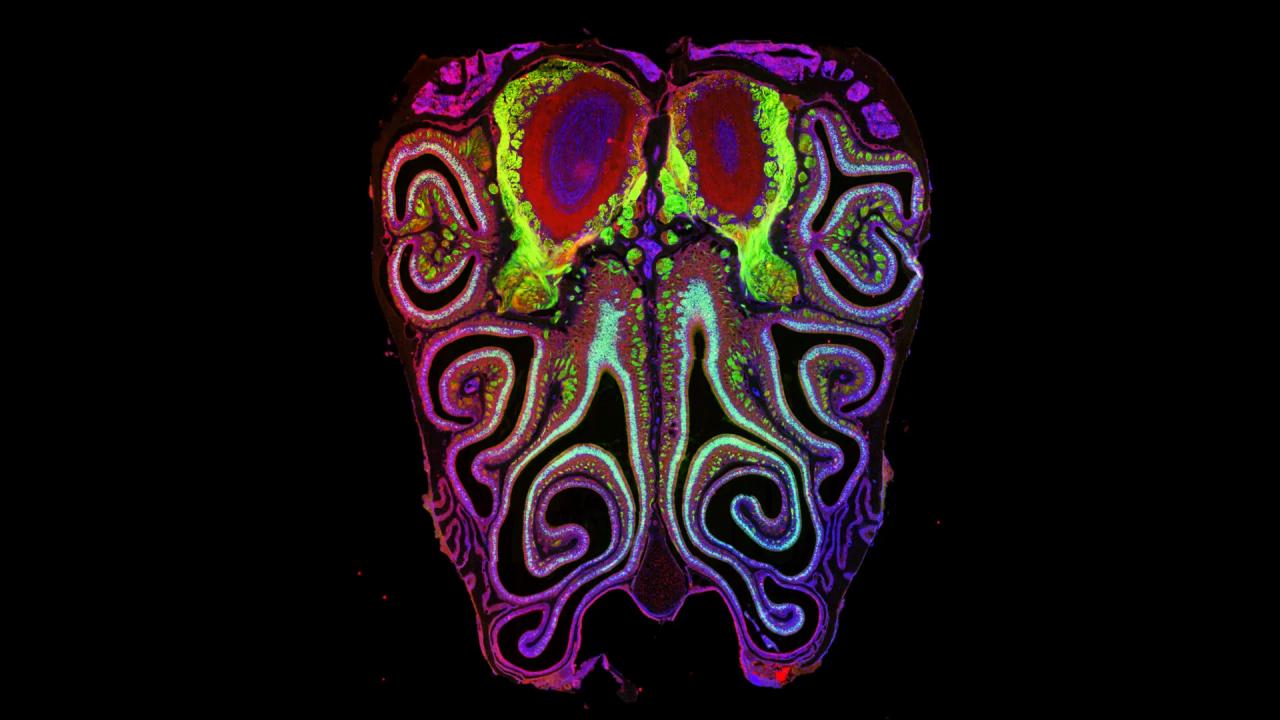

A szaglás mindennapi életünkre is komoly hatással van: észrevehetjük a veszélyforrásokat, meghatározza az ételek ízét, sőt, az emlékekhez és az érzelmekhez is szorosan kötődik. Mégis, az alapvető működési elveiről eddig csak homályosan tudtak a kutatók. Most egerek orrának vizsgálatával sikerült elkészíteni az első részletes térképet arról, hogyan oszlanak el a több mint ezerféle szagreceptort hordozó sejtek. A várakozásokkal szemben ezek a sejtek nem véletlenszerűen helyezkednek el, hanem a receptor típusa szerint csoportosulnak, vízszintes – az orr tetejétől az aljáig húzódó – sávokat alkotva. A mintázat minden egérben szinte teljesen azonos volt, és pontosan megfelelt a szagok feldolgozására szolgáló agyi területek szerkezetének.

A többéves keresés után most sikerült felfedni, mi szabályozza ezt az elképesztően pontos elrendeződést. Az egyik kulcsszereplő a retinsav nevű molekula, amely génműködést szabályoz az orrban. Ennek koncentrációja meghatározza, hogy az egyes szaglóidegsejtek milyen receptort fognak kifejezni: ha a kutatók módosították a retinsav szintjét, az egész receptor-térkép eltolódott felfelé vagy lefelé az orrban. Ez az eredmény is igazolja, mennyire precízen képes a fejlődés során a szervezet beállítani a több mint ezerféle szagreceptor-sejttípus helyét. Később egy másik, független kutatócsoport hasonló eredményekre jutott.